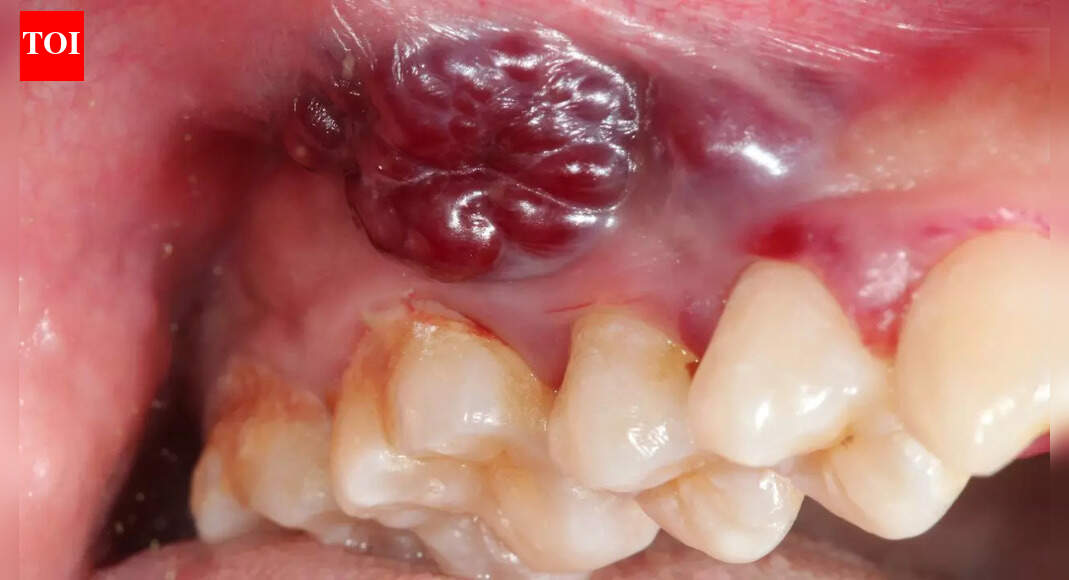

Indian women and growing oral cancer cases: Why a non-healing mouth ulcer could be the earliest red flag

A persistent mouth ulcer, often dismissed, is a critical early warning sign of rising oral cancer rates among Indian women. This often painless symptom, lasting over two weeks, demands immediate medical attention. Lifestyle changes and a lack of awar…